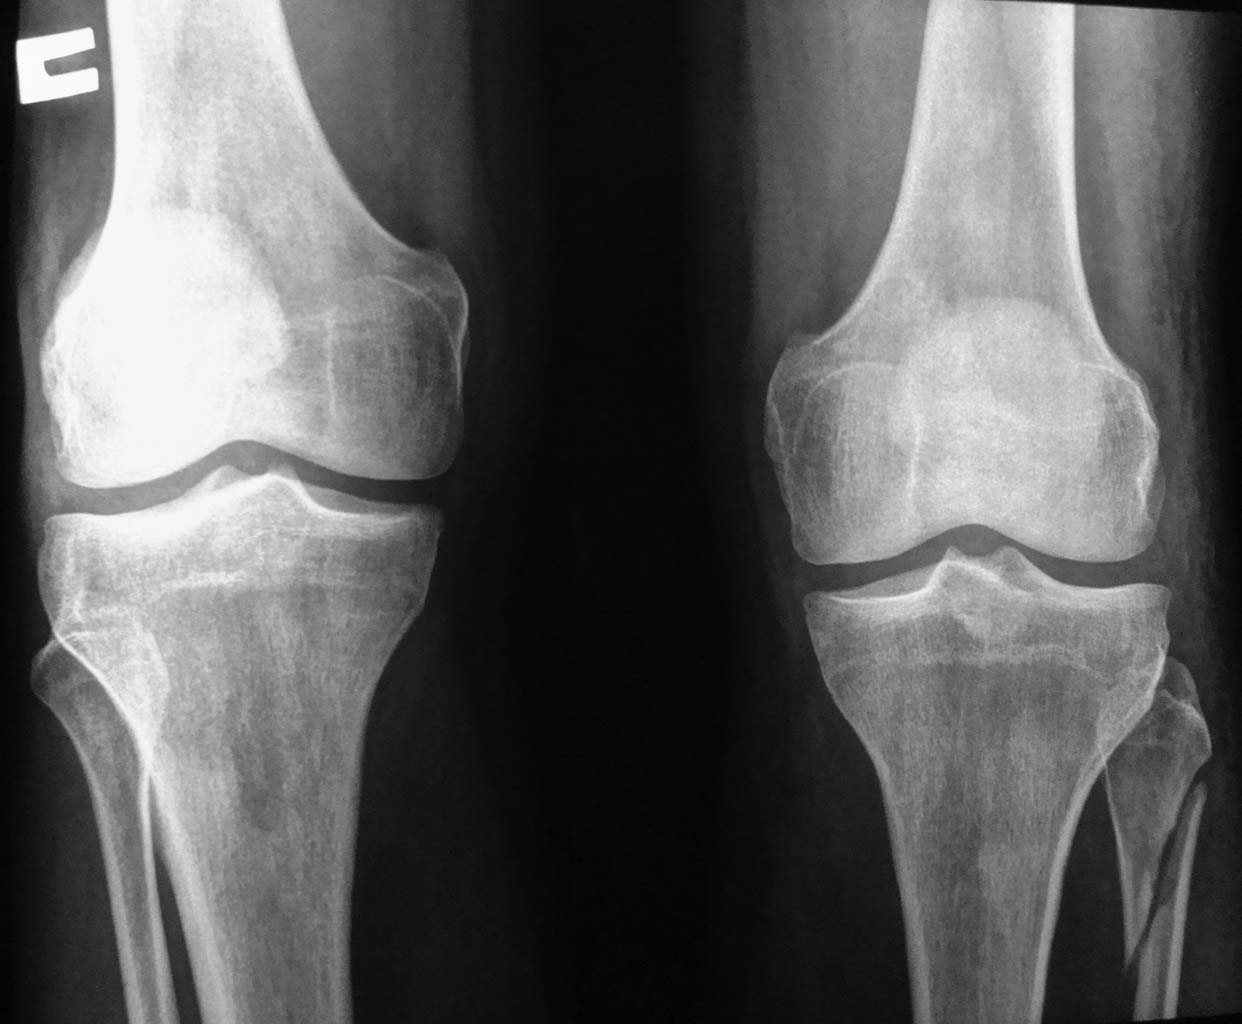

The Maisonneuve fracture is a spiral fracture of the proximal third of the fibula associated with a tear of the distal tibiofibular

syndesmosis and the interosseous membrane. There is an associated fracture of the medial malleolus or rupture of the deep deltoid ligament.